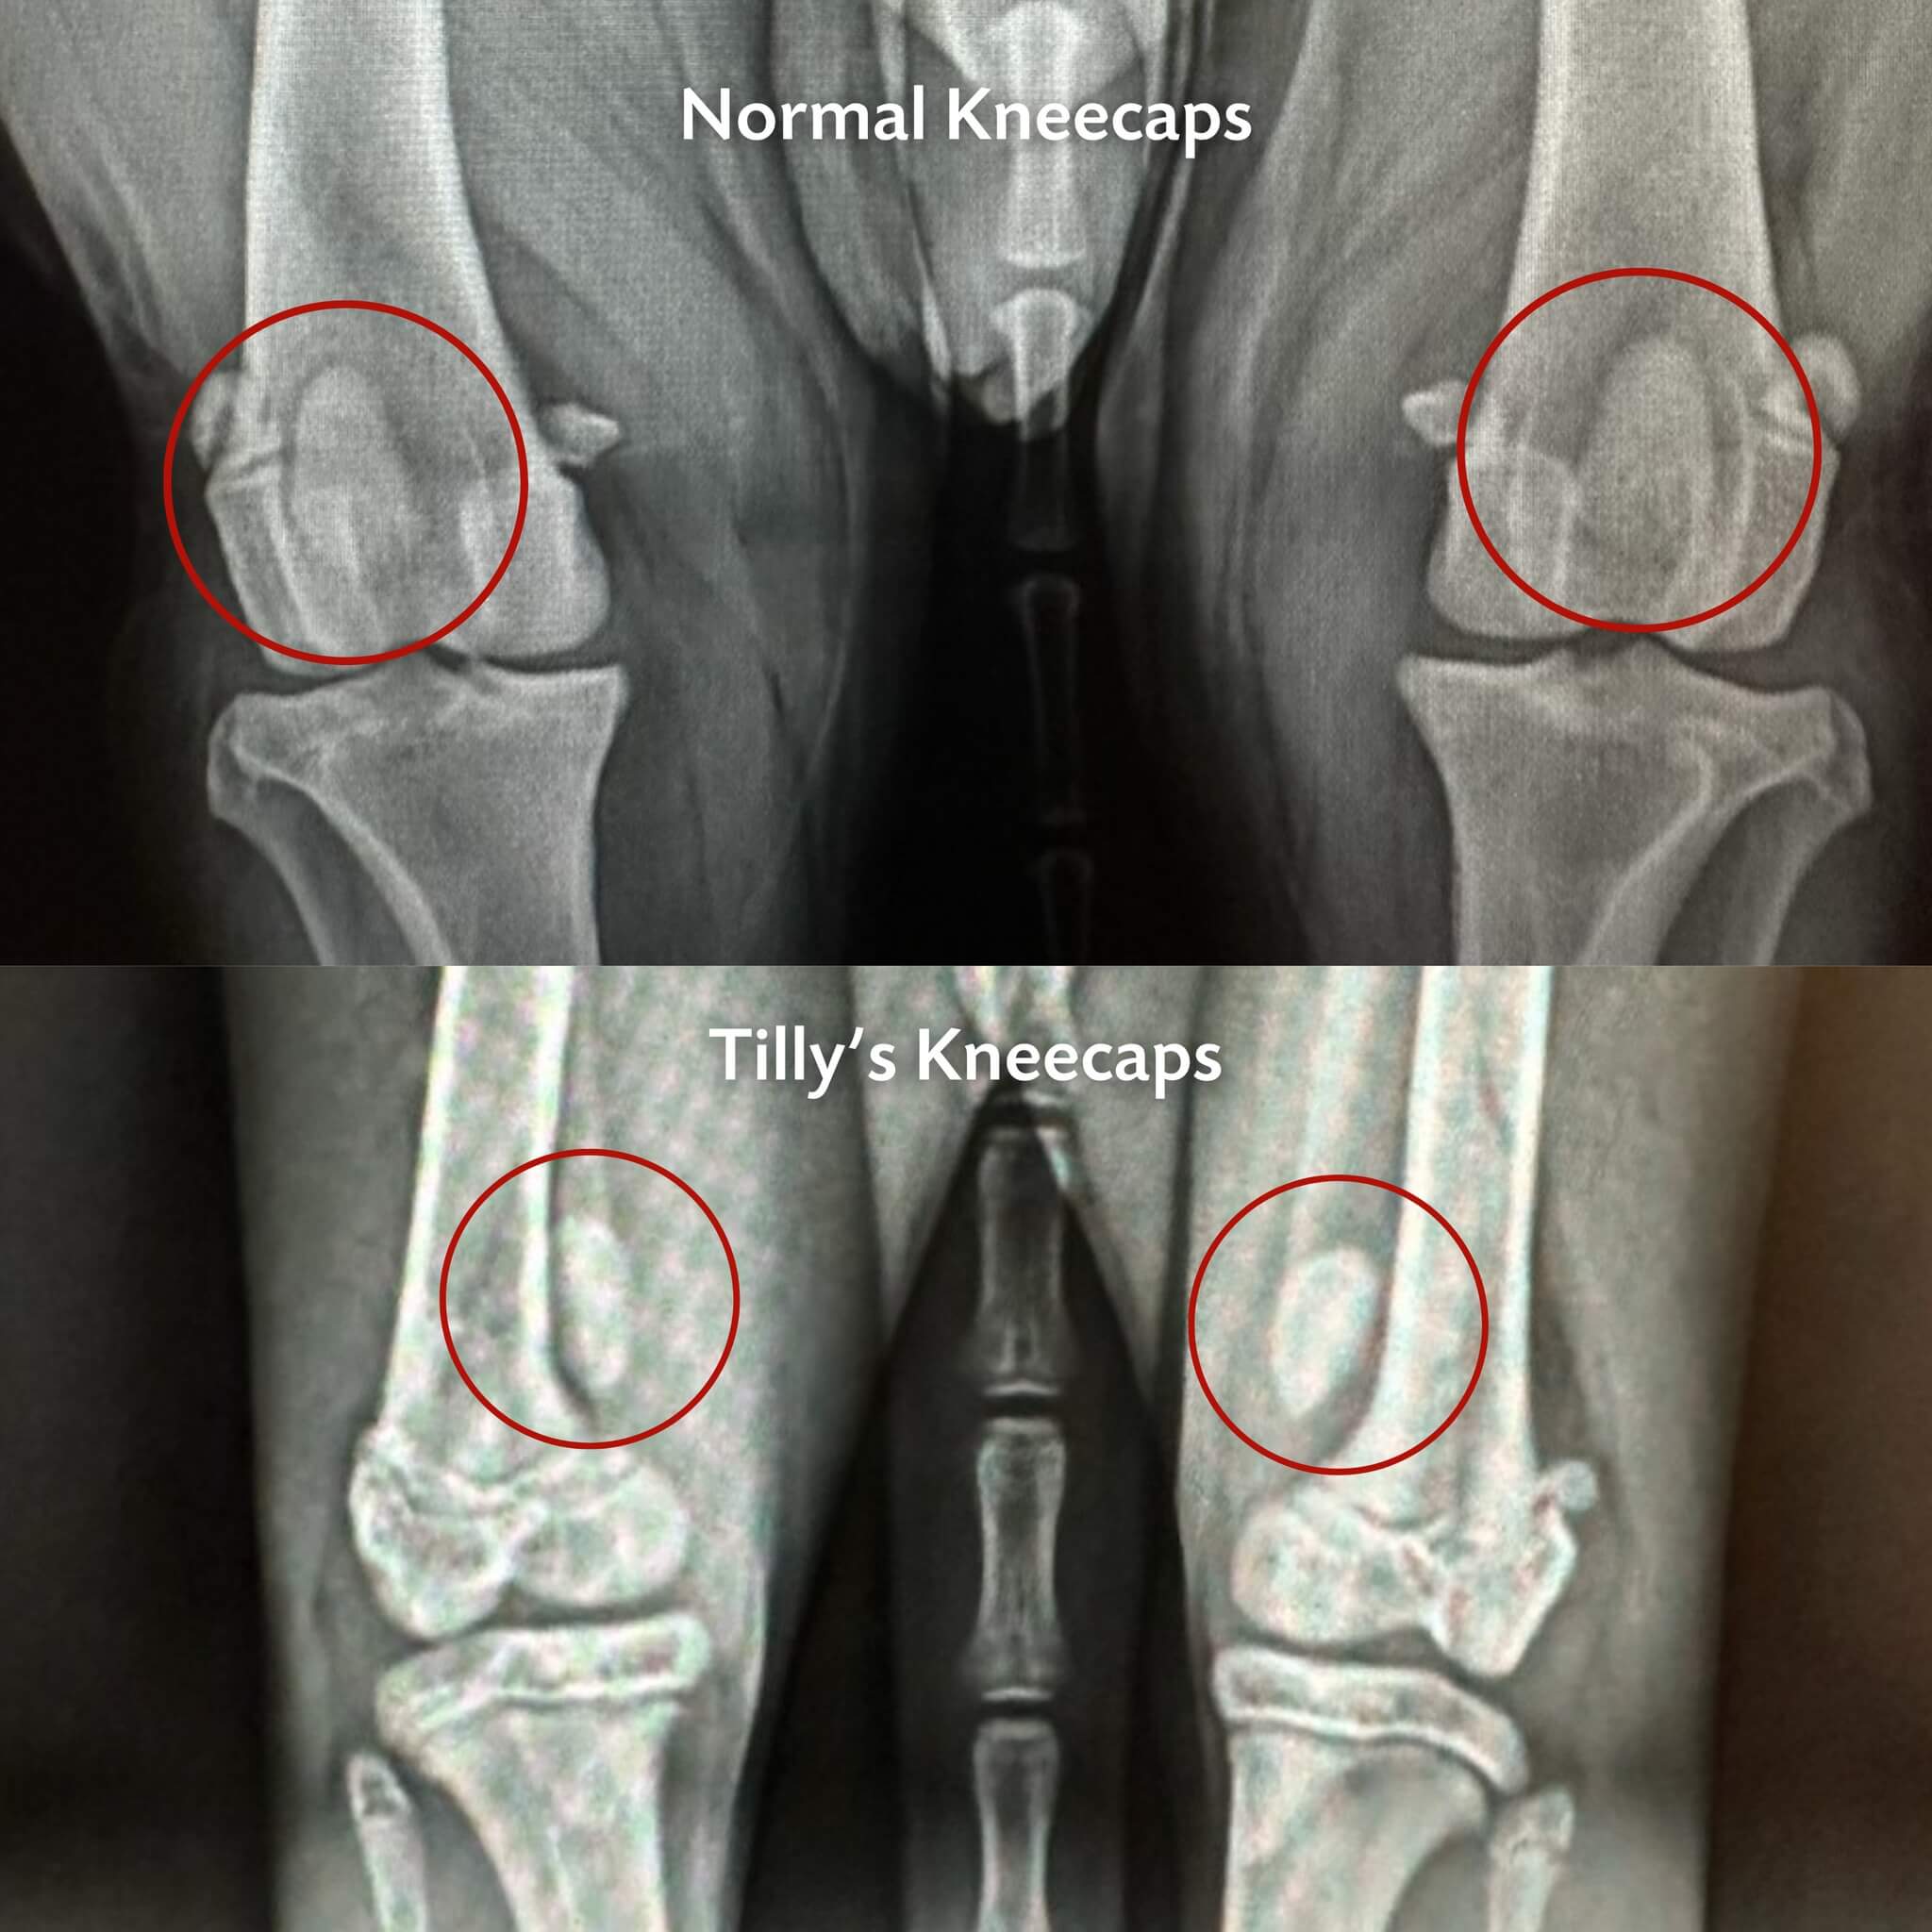

Just when things were finally looking up, Tilly started walking strangely and favouring her back legs. Radiographs revealed the cause: her kneecaps had slipped out of place, a condition called medial luxating patella.

Tilly was placed in a long-term foster home while our team consulted with orthopedic specialists about her future. Surgery was a possibility, but since she wasn’t in pain, the best plan was careful monitoring while she continued to grow.